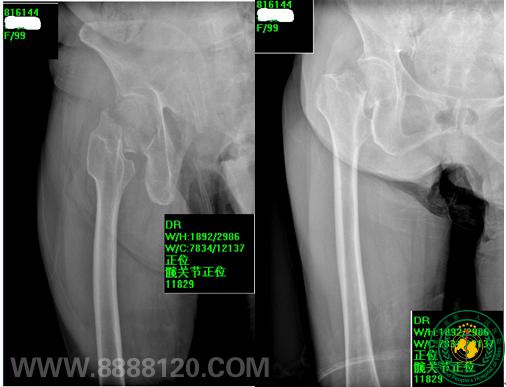

术前X线:我科顺利完成99岁高龄患者人工髋关节置换术一例

术前股骨颈侧位X线                  术前股骨颈正位X线